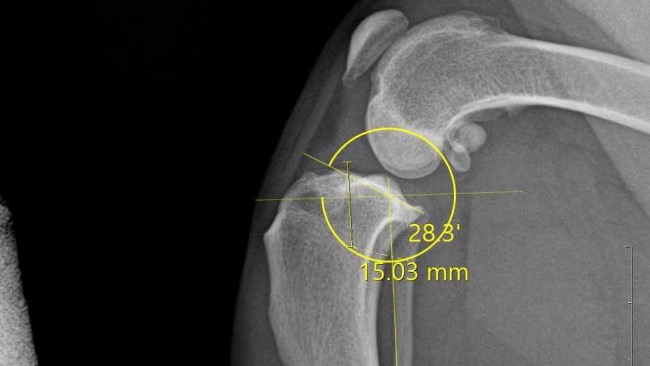

Początkowo pojechalam z partnerem do weterynarza ktory po konsultacj z nami i zbadaniu pieska podejrzewał zerwanie więzadła krzyżowego. Weterynarz skierował nas na prześwietlenie łapki oraz badania krwi do Dr. Gierek w Katowicach. Niestety obawy naszego weterynarz się potwierdziły okazało się ze musi mieć jak najszybszą operacje ponieważ gdy nie zoperujemy zerwanego więzadła piesek będzie cierpiał i jednocześnie obciążał mocno druga tylnią łapkę i może dojść do zerwania więzadła w drugiej łapce a wtedy nasz piesek już nie będzie mógł biegać.

Całą zebrana kwotę przekażemy na operacje naszego psiaka. W załączniku udostępnione są wyniki oraz zdjęcie łapki